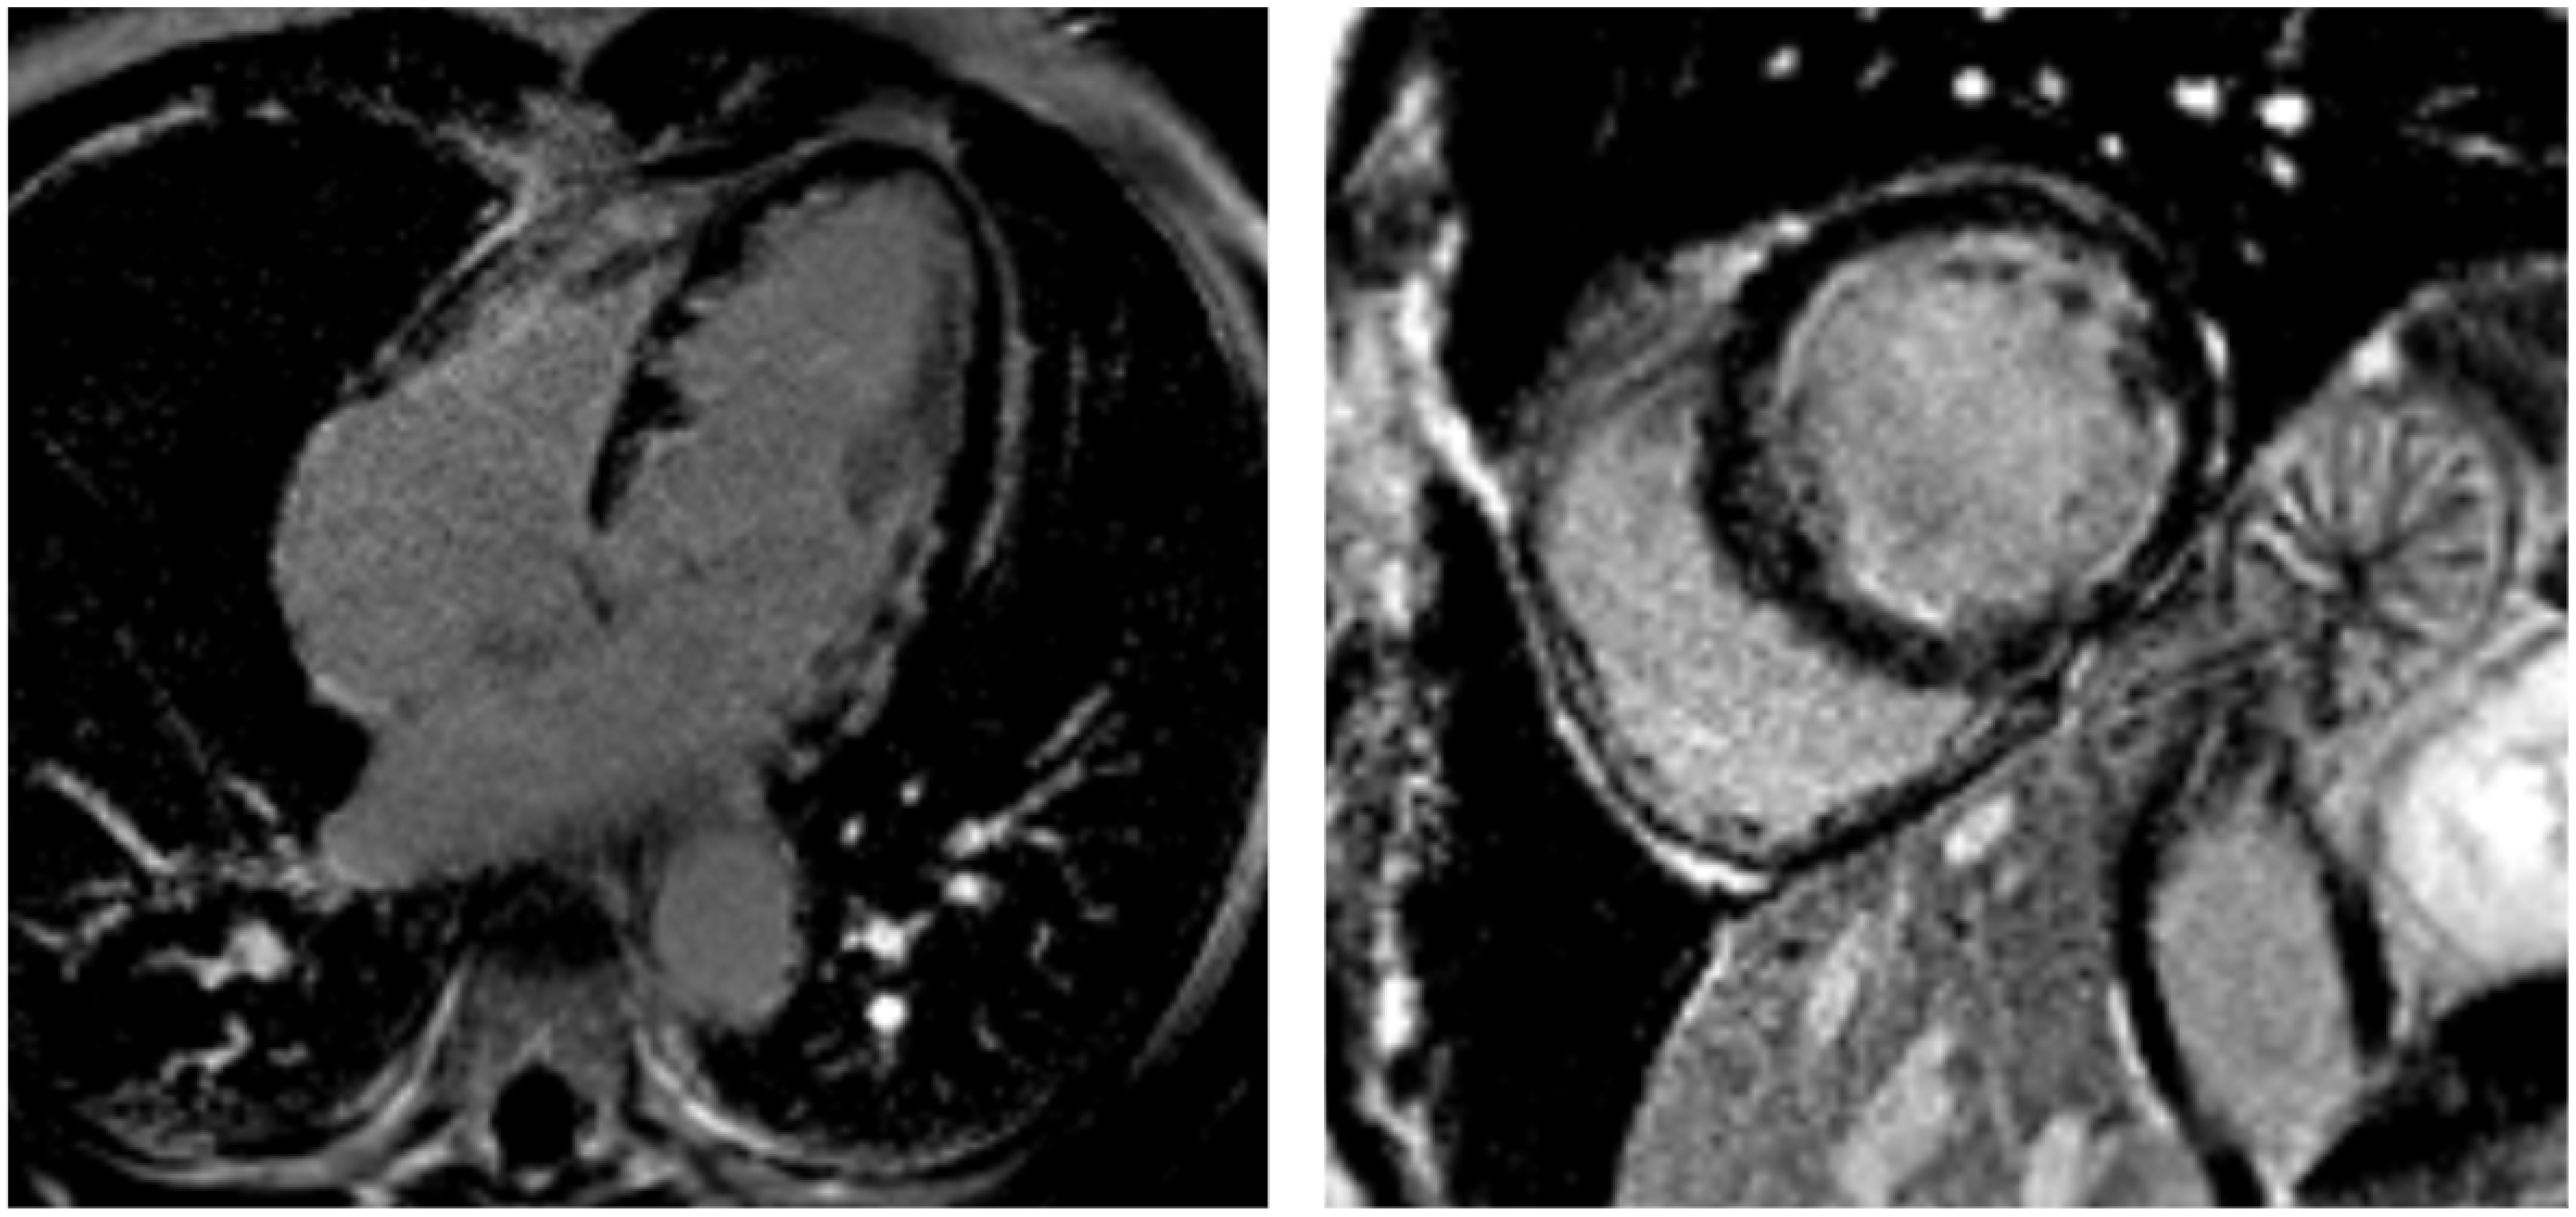

Figure 4.

Loeffler cardiomyopathy. LGE sequences performed 5 months after the onset of eosinophilic myocarditis show a circumferential pattern of subendocardial fibrosis (hyperintense areas) in the apical four-chamber view (left) and mid-ventricular short-axis view (right). The subendocardial fibrosis does not follow a coronary distribution and produces a “V-shaped” appearance of the apical ventricles in the apical four-chamber view.